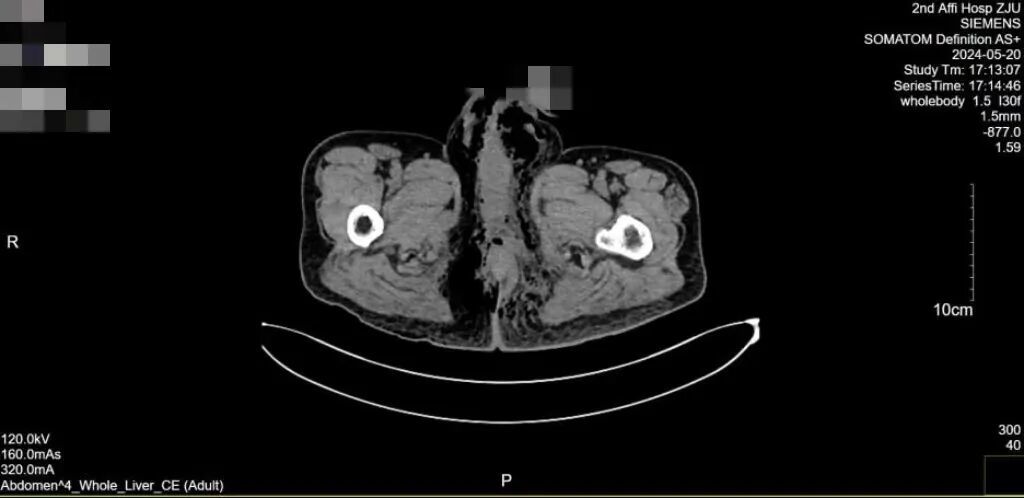

当来到浙江大学医学院附属第二医院急诊时,患者的情况已经相当复杂:全腹 CT 增强扫描提示直肠左侧壁不连续,周围渗出、积液积气,直肠周围筋膜增厚,盆底周围、会阴渗出、积气,两侧腹股沟区、盆壁、左侧腹腔多发积气。

患者腹部 CT 增强扫描报告